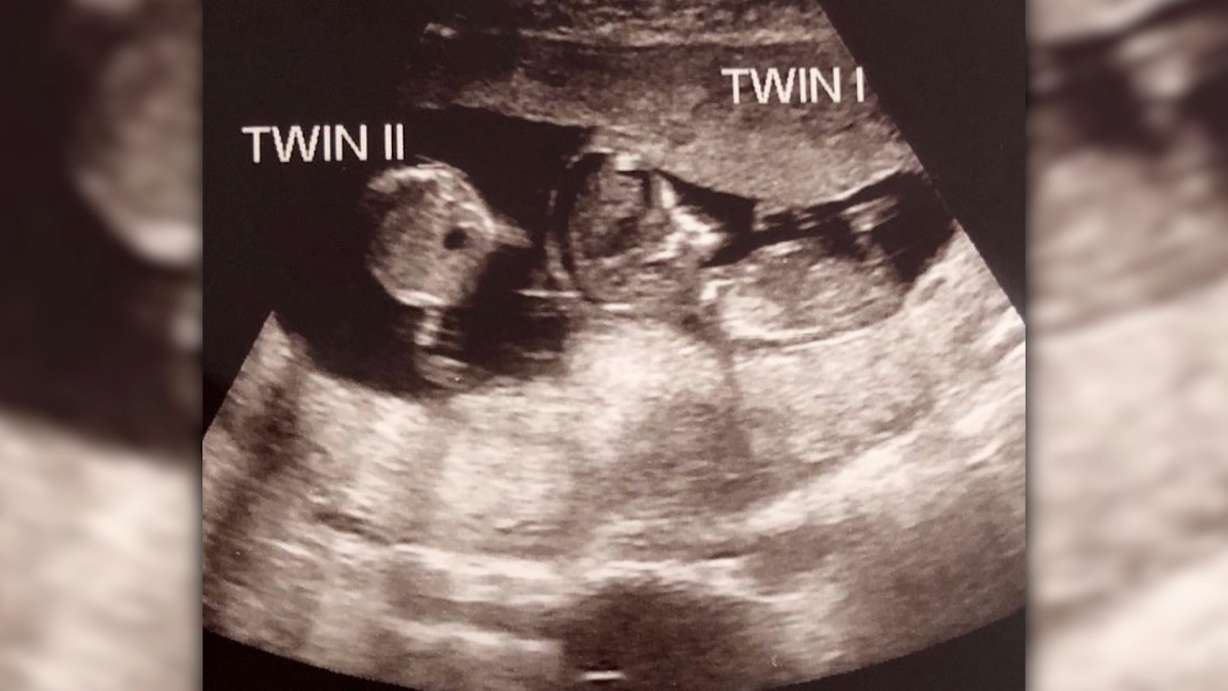

An ultrasound taken at week 12 showed that Noah had an unexpected little sister — fraternal twin Rosalie.

Doctors told the couple the babies were actually conceived about three weeks apart, Rebecca said.

"They realized that the baby was growing at a consistent rate of three weeks behind the first one, and it was then that they said to me, they think this is a superfetation pregnancy," she said.